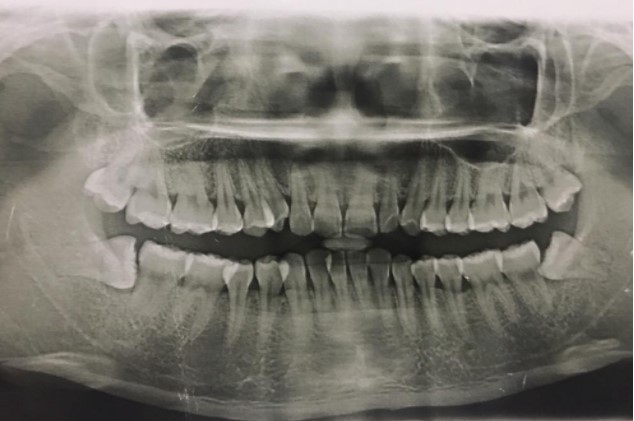

患者,男,38歲。上前牙變色1年,自述上前牙5年前受過外傷,唇側(cè)傾斜,檢查可見左上1牙冠變色,牙冠缺損近1/2,牙髓測試無反應(yīng),X線根尖片顯示患牙無明顯異常,全景片顯示雙側(cè)下頜智齒近中阻生,之前有發(fā)炎化膿病史,目前無咀嚼不適??谇黄溆酂o異常。

檢查情況及X線片見下圖:

(2)檢查見左上1牙冠變色,牙髓測試無反應(yīng),牙冠缺損近1/2,X線片無明顯異常。

非主訴疾病的診斷依據(jù):X線全景片顯示雙側(cè)下頜智齒近中阻生。